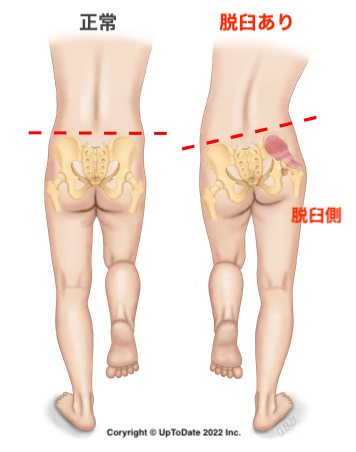

姿勢

片足立ちで骨盤の位置をみる

片足でまっすぐ立ちます。正常であれば骨盤は水平ですが、脱臼があると骨盤の筋力低下により、反対側の腰が下がります(イラスト参照)。

右の脱臼なら左が下がり、両側の脱臼なら左右の立っている足の反対側の腰が下がります。

歩き始めてからは、姿勢と歩き方をみます。

姿勢

片足立ちで骨盤の位置をみる

片足でまっすぐ立ちます。正常であれば骨盤は水平ですが、脱臼があると骨盤の筋力低下により、反対側の腰が下がります(イラスト参照)。

右の脱臼なら左が下がり、両側の脱臼なら左右の立っている足の反対側の腰が下がります。